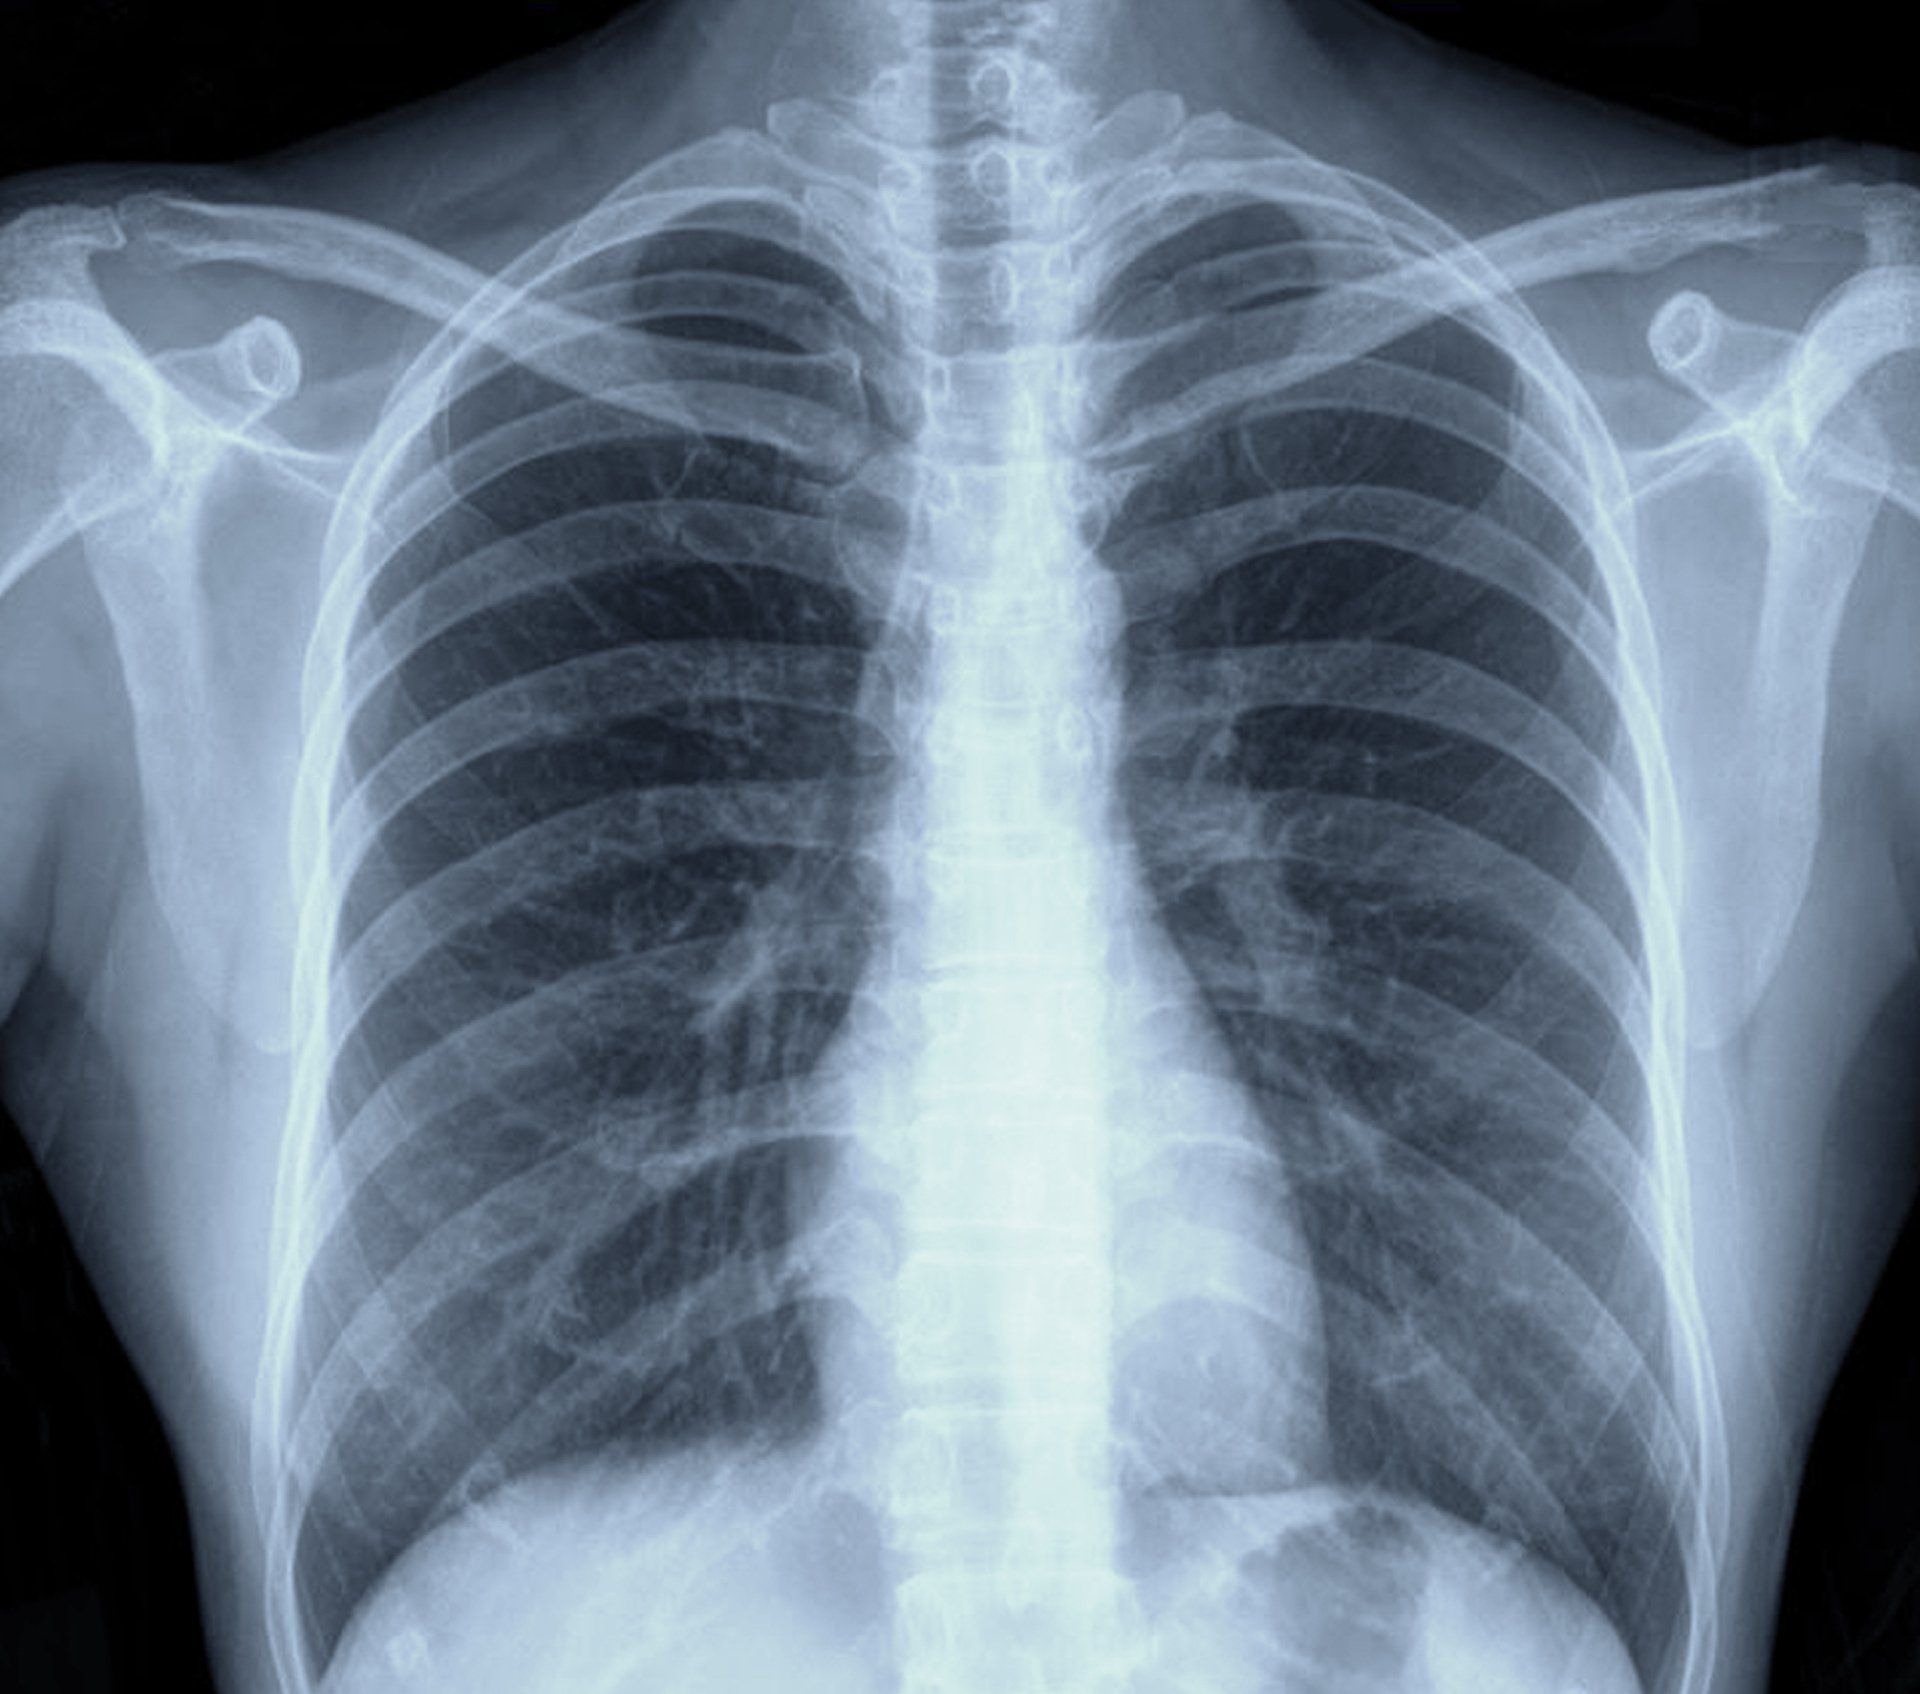

O Dr. Ricardo Terra é formado em medicina pela Faculdade de Medicina da Universidade de São Paulo (FMUSP). Fez residência em Cirurgia Geral e em Cirurgia Torácica no Hospital das Clínicas da Faculdade de Medicina da USP (HC-FMUSP). Concluiu o mestrado na Universidade Harvard e doutorado e livre-docência na FMUSP.

Chefia há mais de 10 anos a equipe de cirurgia torácica do Instituto do Câncer do Estado de São Paulo (ICESP), onde acumulou extensa experiência em cirurgia para todos os cânceres torácicos, em especial para o câncer de pulmão e o timoma.